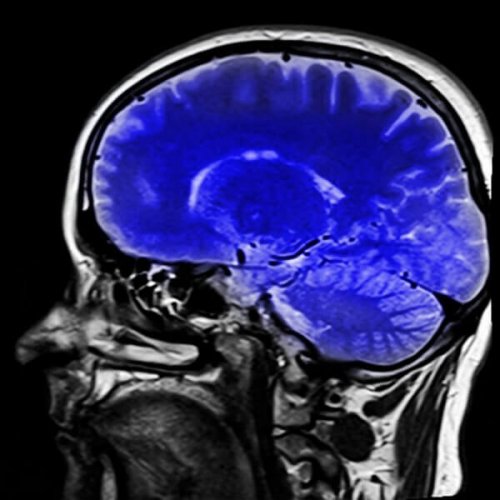

Bildgebende Verfahren können zeigen, welche Art von Hirnläsion gegeben ist, und das wird ihnen helfen, festzustellen, ob es sich um das Gefangensein-Syndrom oder eine andere Kondition handelt. Weiterhin gibt es Testverfahren, die Ärzten helfen, die Hirnaktivität zu evaluieren. Sowohl die Positronen-Emissions-Tomographie (PET) als auch das Elektroenzephalogramm (EEG) können dem Arzt Informationen über die Gehirnaktivität des Patienten liefern. Ein PET-Scan lässt uns sehen, ob der Hirnstoffwechsel normal ist. Und wenn das der Fall ist, würde das bedeuten, dass wesentliche Gehirnfunktionen erhalten sind und der Patient bei Bewusstsein ist, wie beim Gefangensein-Syndrom zu erwarten ist. Mit einem EEG können die Hirnströme des Patienten analysiert werden. Im Falle eines Gefangensein-Syndroms wäre ein normaler reaktiver Alpha-Rhythmus zu sehen.